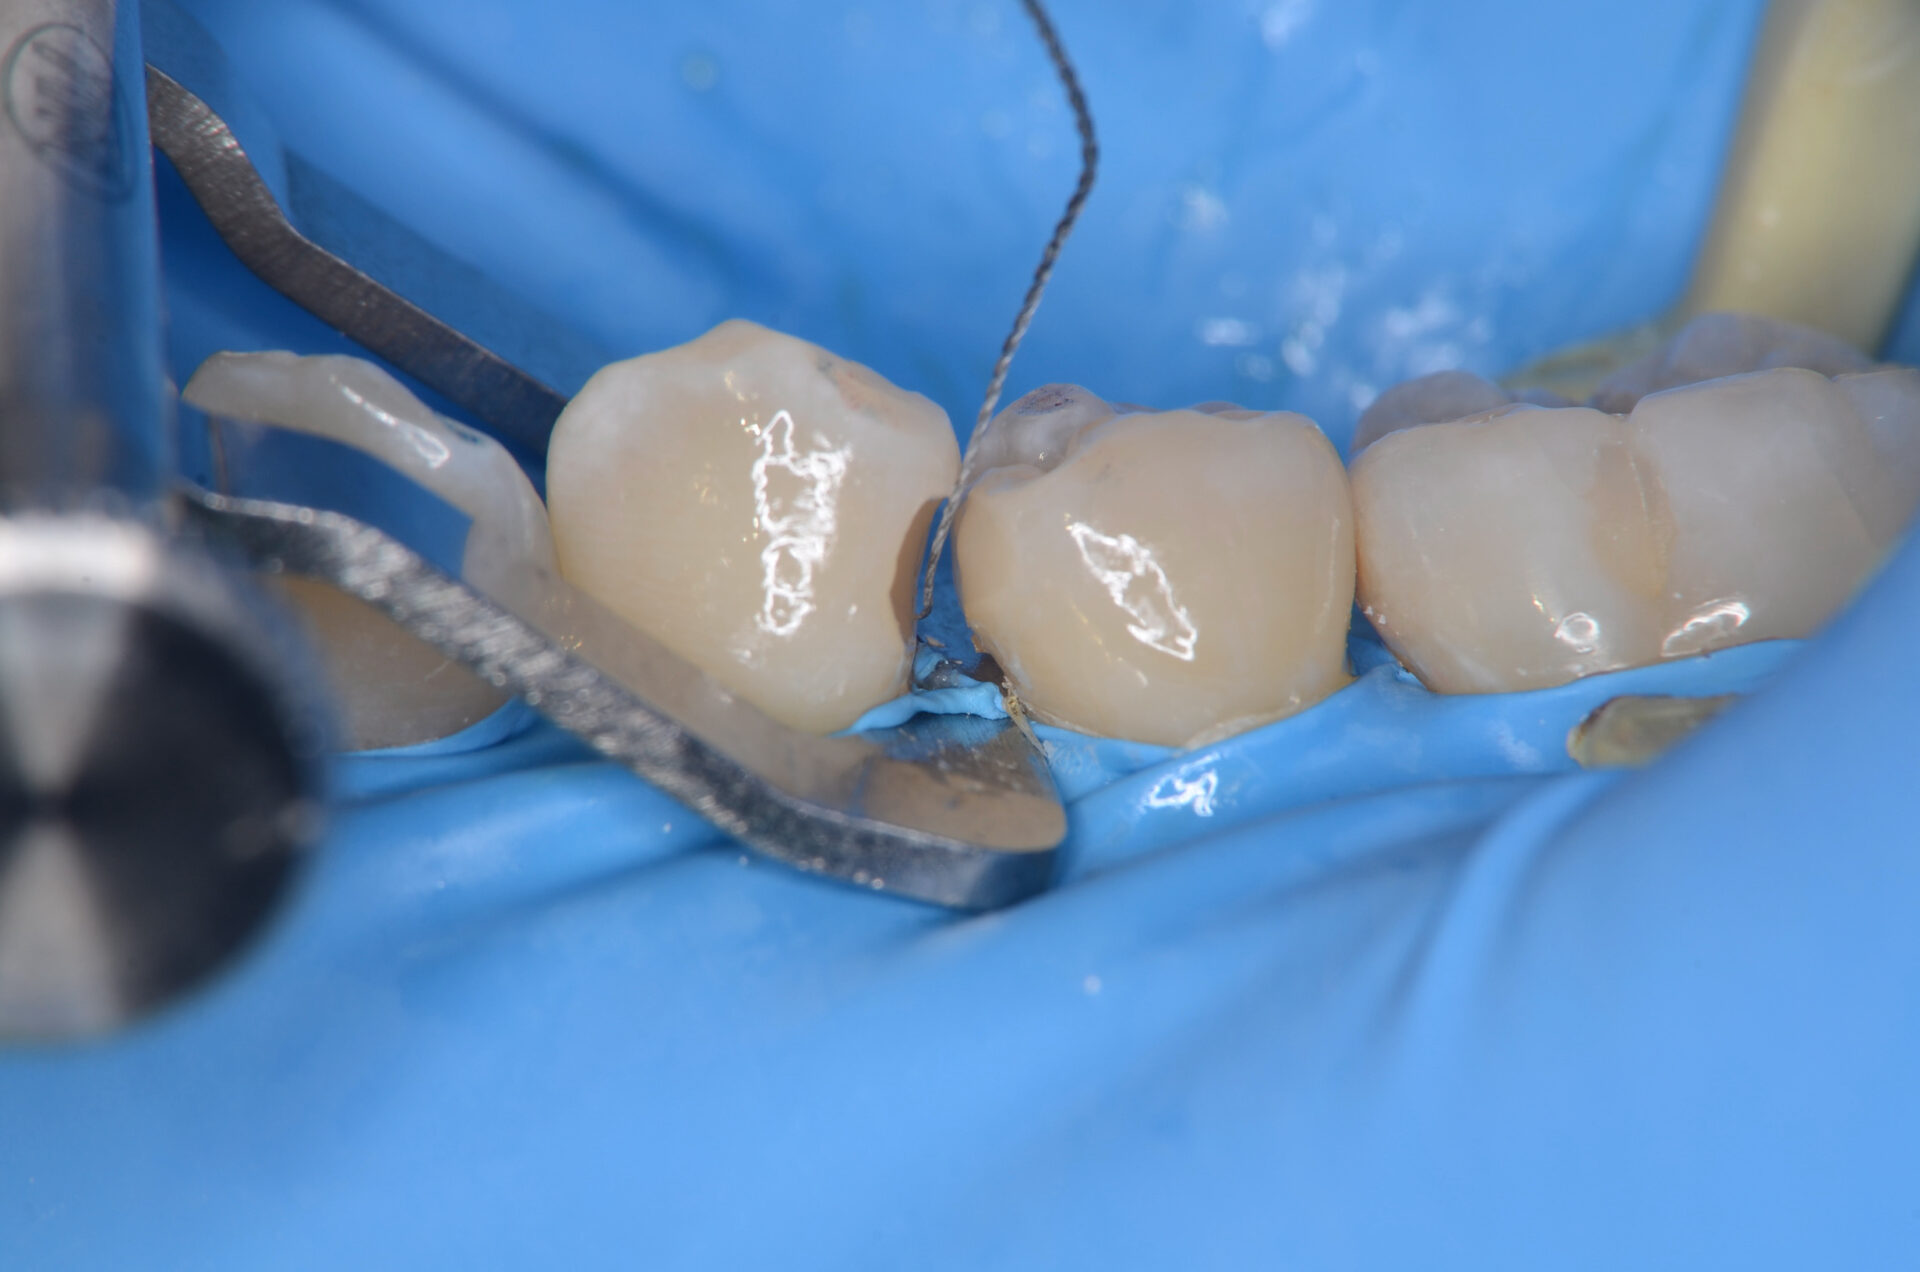

4番ダイレクトボンディング

フロワブルレジンを用いて充填します。重合収縮をできるだけ抑えるために少しづつ積層充填しています。 -

セパレーター設置

セパレーターを使って、1ミリ程、歯間を離開させます。フロワブルレジンの表面張力を利用して滑らかな曲線をつくります。 -

レジン充填完了

フロスを通してみて適切な、きつさがあるのを確認しています。 -